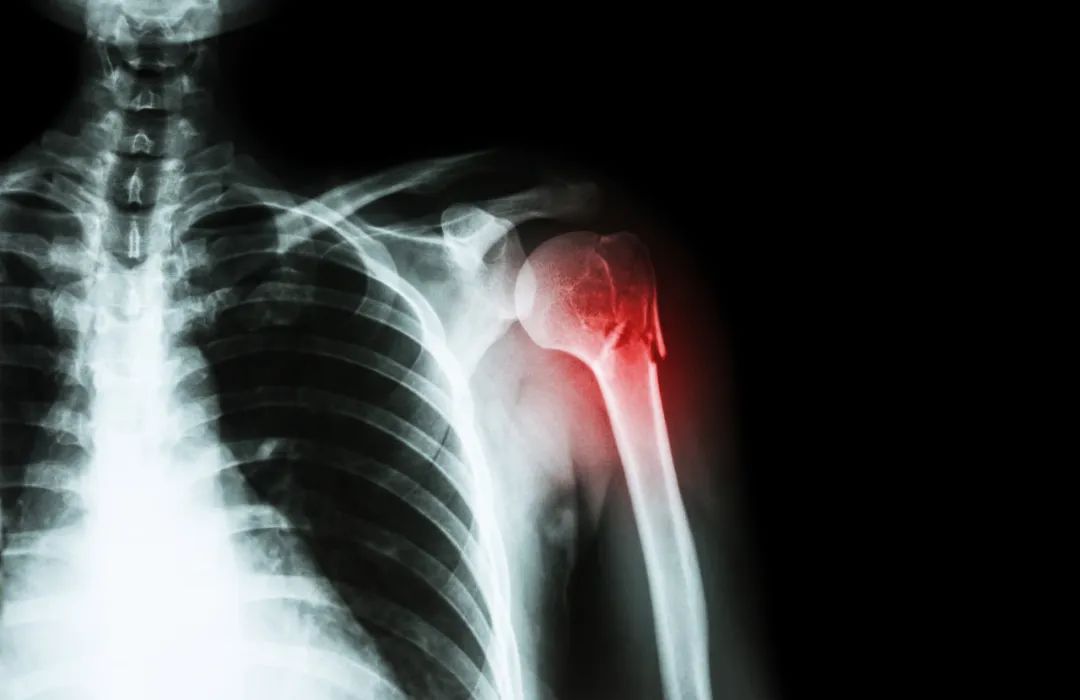

PRP治疗肩袖损伤

肩袖损伤是临床常见却易误诊的一类损伤,其治疗以传统保守治疗为主,效果常不理想。Rha等对39例肩袖损伤患者研究发现,PRP注射疗法较干针疗法显著改善疼痛和肩关节活动功能。然而,亦有研究发现,PRP无法显著改善此类患者第6周及第12周后的疼痛VAS评分、生活质量和肩关节活动障碍。目前,PRP治疗肩袖损伤的高质量临床研究较少,且相关研究结论并不一致,其临床疗效值得进一步研究。